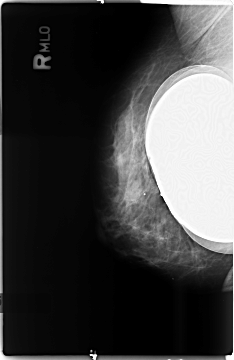

B_3497_1.RIGHT_MLO

RIGHT_CC LINES 4648 PIXELS_PER_LINE 3048 BITS_PER_PIXEL 12 RESOLUTION 50 NON_OVERLAY

RIGHT_MLO LINES 4680 PIXELS_PER_LINE 3040 BITS_PER_PIXEL 12 RESOLUTION 50 NON_OVERLAY